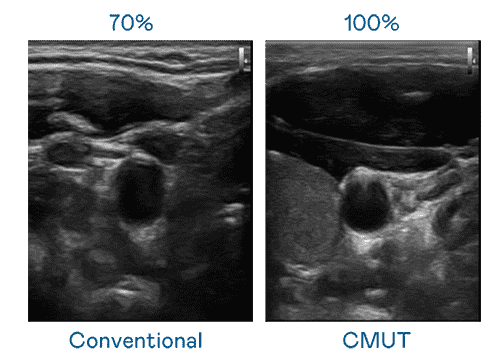

CMUT 技术是一种用电容式微机电元件来产生超音波讯号的技术。。与传统 PZT 压电式技术相比,,,CMUT 频宽增加 30%,,更宽频的超音波讯号让影像解析度大幅提升,,,,是实现高影像品质医疗超音波扫描、、、促进精准医疗发展的关键技术。。

大频宽带来超清晰影像

超音波影像的解析度高低,,,首先取决于探头能发出的讯号频宽。。。万利 CMUT 可提供高清晰的超音波讯号,,,,提供高频宽、、高灵敏度、、、、影像纹理细节更高的超音波影像,,,,协助医护人员缩短影像判读时间及利用精准的医疗影像进行诊断。。。。